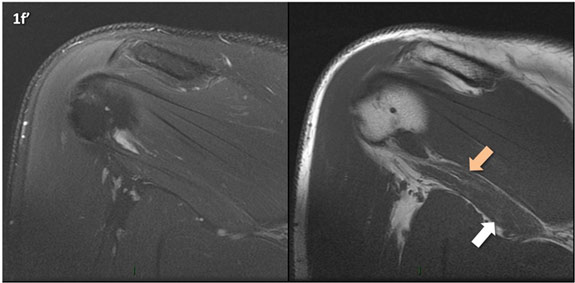

Figura 1 (a-g)': Imagens consecutivas de RM no plano coronal nas ponderações DP com supressão de gordura (DP SG) à esquerda e T1 à direita mostrando . Clique na seta para passar as imagens.

Figuras 1b’ a 1g’ mostrando atrofia da porção superior do músculo redondo menor (seta salmão), com lipossubstituição mais evidente das mais fibras laterais (seta amarela). As fibras mais inferiores e mediais têm atrofia menos evidente.

Repare que estas alterações não são evidentes nas imagens com supressão de gordura.

Chafik et al. também relataram a presença de um pequeno nervo motor acessório em número variável que se insere na porção lateral do músculo redondo menor. O nervo acessório, ao contrário do principal, tem um curso reto e extra-fascial, sendo menos vulnerável aos efeitos compressivos. De fato, nos casos da atrofia parcial do redondo menor, é mais frequente a atrofia da porção mediodorsal com preservação da porção lateroventral, o que poderia ser explicada pela presença do ramo acessório mais lateral do nervo axilar, embora atrofia isolada do componente lateroventral tenha sido reportada em cerca de 17% dos casos de atrofia de apenas uma porção, o que pode ter sido causada por lesão do nervo acessório. No caso do paciente deste mês, a atrofia é mais evidente nesta porção mais lateral e ventral do redondo menor.